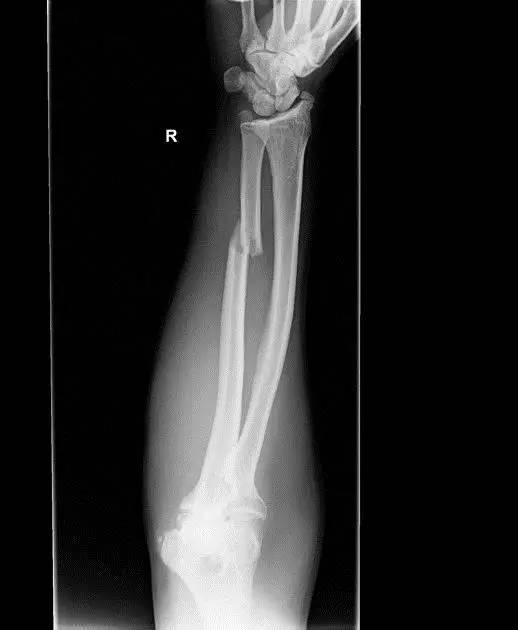

11. Nightstick 骨折(警棍骨折)

直接外伤造成尺骨单骨折。前臂单纯的尺骨骨折,通常是由钝伤造成。Nightstick 的意思是警棍,此伤害可因受到棍击时举起手来抵挡产生。

(来源:Radiopaedia)